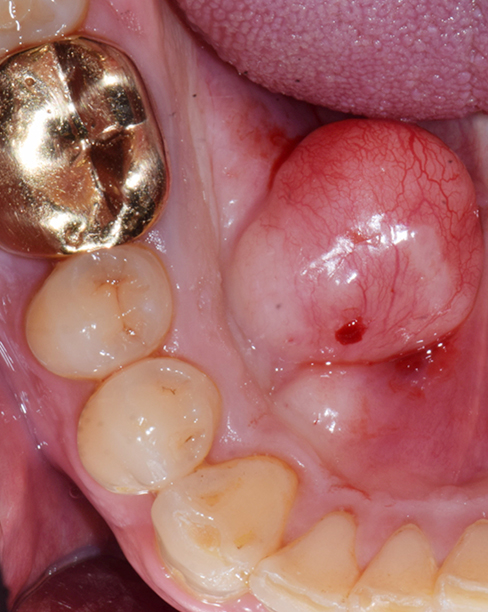

A surgical procedure to remove tori

Tori do not have to be removed in most cases. Tori are removed to accommodate upper or lower dentures.